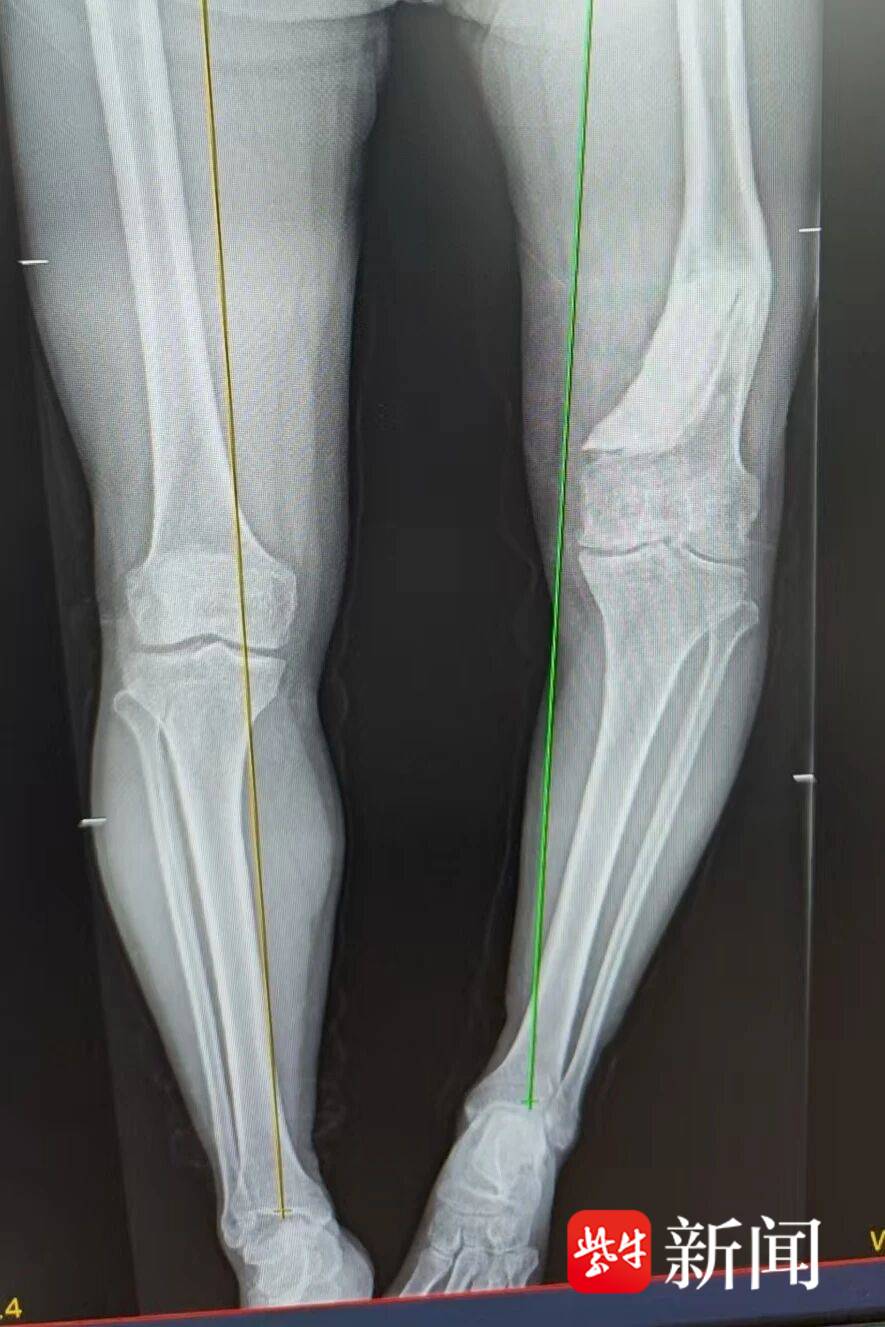

患者术前腿部影像

“患者需要同时经历两个大手术,我们就像是跟死神‘扳手腕’。”袁永建形容道,“患者左腿比正常的右腿短了6cm,崩断任何一个神经、血管,手术就失败了!”术前,袁永建带领团队周密计划,制定详细的手术方案,反复演算、模拟,确保手术达到理想效果。

1月16日,在手术部的协同下,团队为束师傅开展“截骨矫形+单髁置换术”。手术需要在畸形最严重的部位截去部分组织,参照右腿的长度和角度进行矫正,确保力线与右腿平行,再置换病变的膝关节,可谓“步步惊心”。在团队的密切配合下,原本计划五个小时的手术,实际三个小时就完成了。